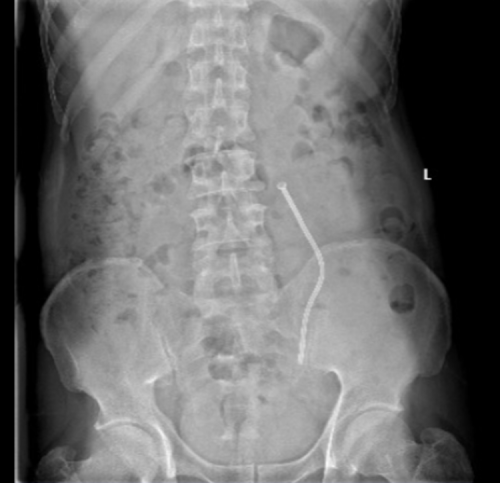

术后患者恢复良好,次日复查肌酐 158umol/l,术后KUB(腹部平片检查)显示:Memokath新型热膨胀镍钛记忆合金输尿管支架,具有遇热膨胀、遇冷变软的物理特性;支架表面覆有特殊涂层,可以减少输尿管上皮细胞生长和结石的形成;且不适反应较小,能大大减轻患者痛苦、改善患者生活质量。